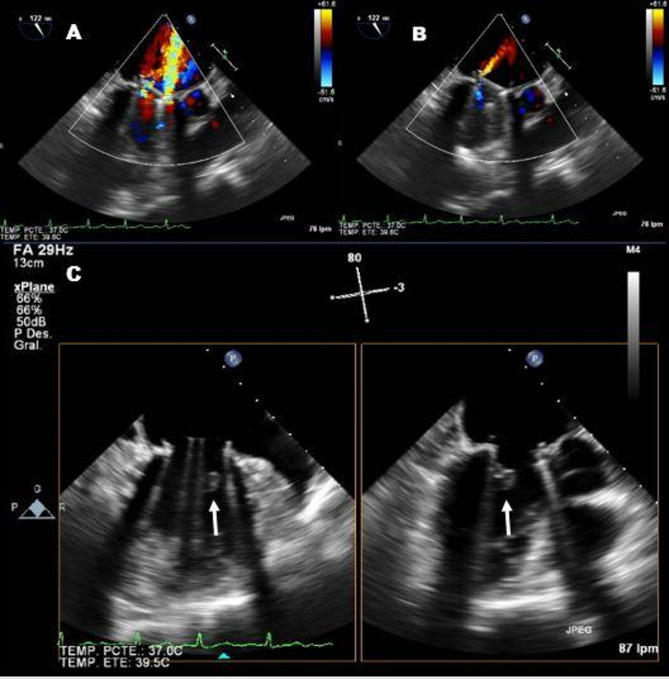

Case presentation: We present the case of a 72-year-old woman with a history of rheumatic heart disease and a mechanical mitral valve prosthesis. Although the initial postoperative course was uneventful, she developed rapidly progressive heart failure symptoms two years after surgery, secondary to newly onset severe mitral regurgitation. Transesophageal echocardiography was crucial in elucidating the underlying mechanism, revealing a ventricular mass intermittently interfering with the proper closure of the mechanical prosthesis. The main differential diagnoses regarding the origin of the mass included: remnants of the subvalvular apparatus, vegetation, thrombotic material and pannus formation. Given the clinical deterioration, surgical intervention was considered necessary despite the lack of precise knowledge regarding the nature of mass. Surgical exploration confirmed the rupture of the subvalvular apparatus involving the anterolateral papillary muscle as the underlying cause of the prosthetic dysfunction. Excision of the ruptured chordae tendineae and residual papillary muscle was performed with a favorable outcome and no complications.

Conclusions: This case illustrates a rare cause of late prosthetic mitral valve dysfunction: the entrapment of the subvalvular apparatus due to spontaneous rupture of the papillary muscle. Transesophageal echocardiography proved highly valuable in understanding the mechanism of dysfunction; however, surgical exploration ultimately established the definitive diagnosis and facilitated the correction of the issue.